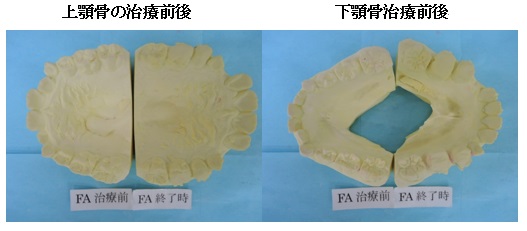

本日ご紹介する症例は7歳の女の子です。典型的な受け口(下顎前突)です。

受け口(下顎前突)だったので上顎骨の成長が抑制されていたために治療後に上顎骨はかなり大きくなっています。

大人ではこの変化は起こりません。次に骨格で比べて診ましょう。

同じ人の1年後の骨格です。

小学校低学年の治療であれば、この変化は普通に起こる変化です。

骨格のことからも受け口は早期治療の効果が得られやすい症例です。